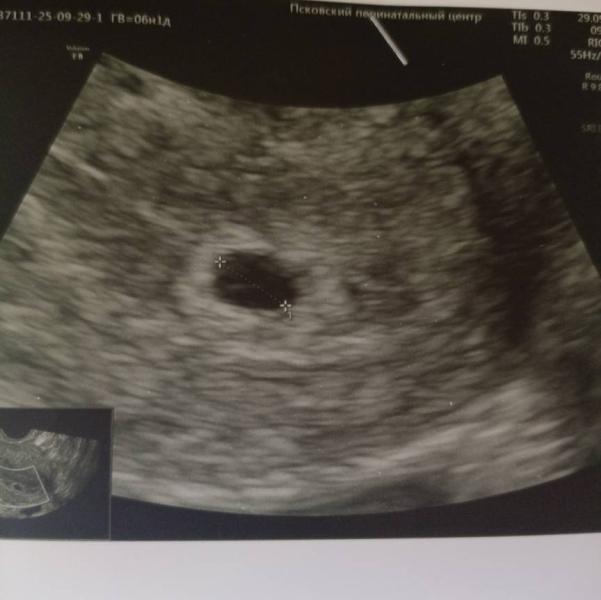

Девы, кто понимает в узи.

Скажите пожалуйста, вы же тоже видите не пустое плодное?

Мне кажется это желточный мешочек, только узистка решила не рассматривать. Она увидела датчиком маточную и сказала все вставай, придешь через неделю 🤦

Главное, что я взяла консультацию у узистки хороший, мне она сказала что аппарат все таки уже старый. И проклёвывается плодной мешочек, плодное не пустое. Уже спокойнее.

Тоже вижу кругляшок у вас ❤️

Слева как будто, что то видно. Может у неё аппарат не совсем новый, вот и не увидела и не стала искать🤷🏻♀️ Сходите к другому врачу на узи.

Слева тоже вижу, что то похожее

@katysha36 спасибо 🙏 взяла консультацию у врача узи, она тоже сказала, что аппарат плохой, но что то видно. Только к сожалению овуляция отслежена от овуляции срок на момент узи 3'6-4 недели